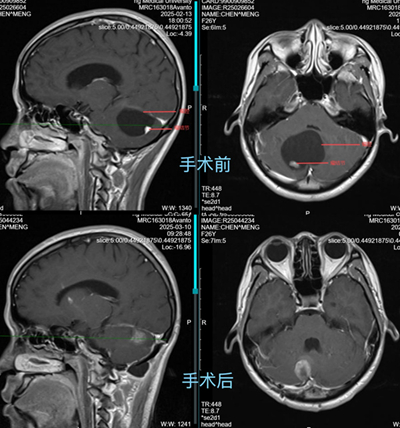

在消化內(nèi)科,小林經(jīng)胃腸鏡、腹部CT等系統(tǒng)檢查后,被告知未發(fā)現(xiàn)消化道病變。那么,到底是什么原因引起小林持續(xù)惡心、嘔吐伴步態(tài)不穩(wěn)呢?此時(shí),重醫(yī)附屬大學(xué)城醫(yī)院消化內(nèi)科團(tuán)隊(duì)捕捉到小林伴隨的共濟(jì)失調(diào)體征?!皣I吐伴步態(tài)不穩(wěn)要警惕神經(jīng)系統(tǒng)病變?!毕瘍?nèi)科醫(yī)生說(shuō)道,隨后,立即啟動(dòng)多學(xué)科會(huì)診。經(jīng)顱腦磁共振成像(MRI)檢查,結(jié)果顯示:小林小腦半球存在巨大的囊實(shí)性占位性病變,是小腦巨大腫瘤。輾轉(zhuǎn)2月,小林的病因終于浮出水面。

手術(shù)前后MRI對(duì)比。重醫(yī)附屬大學(xué)城醫(yī)院供圖

回憶起一個(gè)多月前,小林被轉(zhuǎn)到神經(jīng)外科的樣子,重醫(yī)附屬大學(xué)城醫(yī)院神經(jīng)外科副主任唐榮銳不免心里咯噔一下?!爱?dāng)時(shí)情況非常緊急,她的小腦占位性病變已經(jīng)壓迫第四腦室和腦干,若不及時(shí)手術(shù),可能導(dǎo)致腦干功能障礙、急性梗阻性腦積水等嚴(yán)重并發(fā)癥,甚至危及生命?!苯?jīng)過(guò)急診手術(shù),小林的腦內(nèi)腫瘤被順利切除,徹底解除壓迫,惡心、嘔吐癥狀也很快消失。